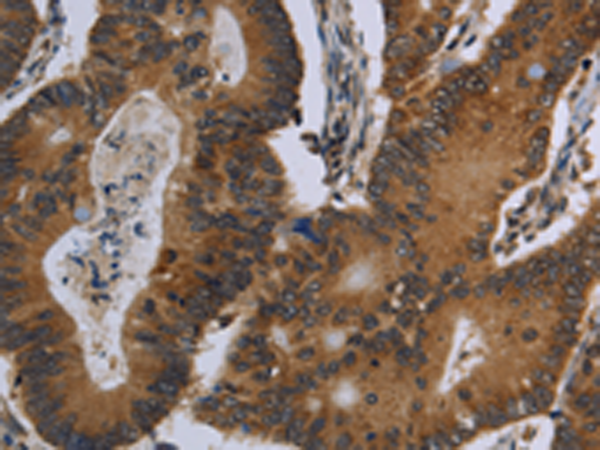

IHC positive control: |

Human colon cancer and human liver cancer |

IHC Recommend dilution: |

25-100 |